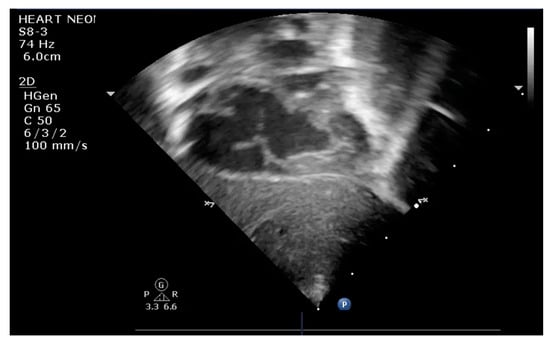

The indication for balloon atrial septostomy was made based on clinical status (low systemic arterial oxygen saturation) correlated with tissue hypoxia (persistently elevated lactate level), echocardiographic assessment (patency and size of interatrial septal defect, ductus arteriosus, and interventricular septal defect), and anticipated delay to surgery. The procedure was performed according to the institutional protocol, at the patient’s bedside, under general anesthesia, and using the Rashkind pull-back technique under echocardiographic guidance (Figure 1 and Figure 2). Vascular access was obtained via a sterile technique via the femoral or umbilical vein. The procedure was repeated several times until satisfactory atrial communication was obtained. The success of BAS was clinically objectified by increasing systemic arterial saturation by at least 10% and echocardiographically objectified by increasing interatrial communication (Figure 3).

Figure 1.

Transthoracic echocardiography (TTE) subcostal view: atrial septostomy catheter in the LA.